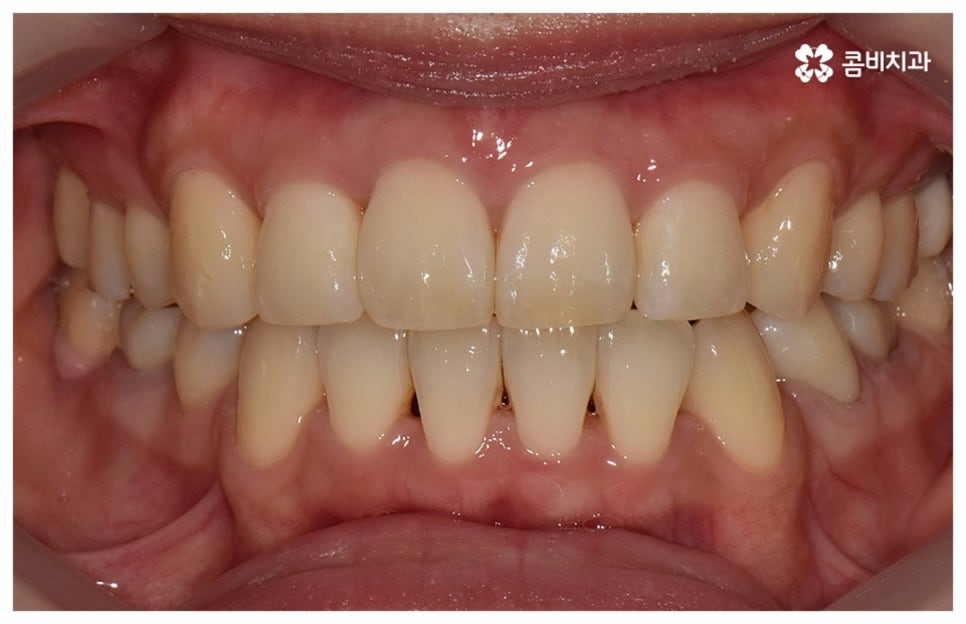

이와 같이 자연스러운 노화로 인한 변화를 주의깊게 신경쓰면서 충분한 시간을 들여 치아를 이동시키는, 다양한 임상 경험이 풍부한 숙련된 의료진이 처음부터 끝까지 세심하게 케어하는 치과에서 함께 하신다면 중년치아교정 치료를 받는 것을 크게 걱정하실 필요는 없을 거예요. 또한 요즘은 정기 검진 및 스케일링 치료와 같은 평상시 관리의 중요성에 대해 정확하게 인지하고 이를 꾸준하게 해주시는 분들이 늘어나 전반적으로 구강 건강 상태의 양호도가 상향되었기 때문에 40~50대 중년치아교정 치료를 받으시는 데 별 무리가 없는 경우가 많으니 ‘이 나이에 교정은 안될 거다’ 라고 지레 포기하지 마시고 검진과 상담부터 차근차근 받아보시길 권유드리고 있어요.

검진 후 부분 교정이 가능하지 않은 케이스라고 해도 요즘은 심미적인 교정 장치가 많이 나와 있으며 장치 자체로 인해 결과에 미치는 영향이 크지 않기 때문에 자신의 상황에 맞는 장치를 직접 선택할 수 있으니 의료진과 충분히 상담을 해 보시면 도움 받아 보실 수 있을 거예요. 특히 치아 색상의 브라켓을 이용한 세라믹 장치들이 심미성이 뛰어난데, 그 중에서도 자가결찰방식을 이용한 클리피씨 교정 장치를 이용하면 눈에 크게 띄지 않을 뿐 아니라 보다 적은 힘으로 부드럽고 지속적인 치아 이동을 가능하게 하기 때문에 통증도 줄이고 전체 교정 기간 역시 단축시킬 수 있다는 장점이 있으니 이에 대해서도 자세하게 알아보시길 바라고 있습니다.

위 사진은 환자분의 동의를 받아 이해를 돕기 위한

사진이며, 실제 치료 결과는 다를 수 있습니다.